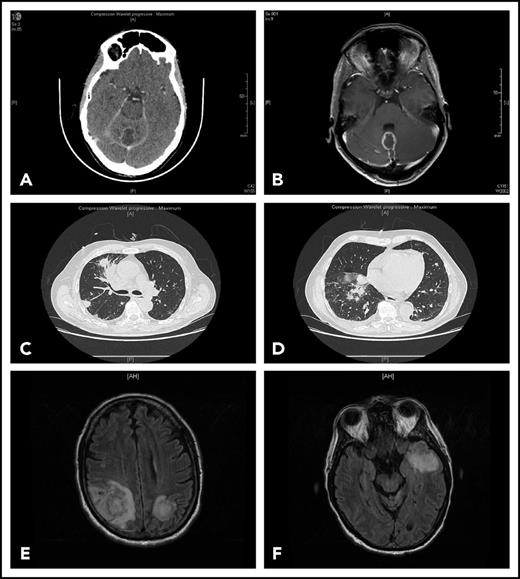

Representative findings in 2 patients with IFI. Patient 1 had been receiving ibrutinib 420 mg/d for 4 months for CLL associated with grade 3 autoimmune neutropenia when she complained of gait disorder. Computed tomography scan (A) and T1-weighted magnetic resonance imaging with gadolinium injection (B) revealed a solitary abscess of the vermis. Neurosurgical drainage disclosed Aspergillus fumigatus. Patient 2 was hospitalized after a third cycle of bendamustine, rituximab, ibrutinib for fever, cough, and confusion. Chest computed tomography scan revealed multiple pulmonary nodules (C-D) and T2-weighted fluid attenuation inversion recovery (FLAIR) magnetic resonance imaging multiple cerebral abscesses (E-F). Aspergillus antigenemia was strongly positive, and Aspergillus fumigatus was isolated in the bronchoalveolar lavage.

Patients’ characteristics are shown in Table 1. Thirty patients had CLL, including 15 with 17p deletion. One had mantle cell lymphoma and 2 Waldenström macroglobulinemia. Median number of previous treatments was 2 (range 0-4). Previous treatments consisted of immunochemotherapy. Three patients had received alemtuzumab >3 years before ibrutinib. None had undergone stem cell transplantation. All but 1 patient received ibrutinib for a relapsed/refractory disease. Median time between last treatment and ibrutinib was 10.5 months (range 1-96). Additional predisposing factors were present in the majority of patients. IA accounted for the majority of IFIs (27/33), including 11 cases (40.7%) with CNS localizations (Figure 1). Using European Organisation for Research and Treatment of Cancer criteria, 17 cases were proven, 9 probable and only 1 possible. We also observed 4 cases of disseminated cryptococcosis, 1 mucormycosis, and 1 Pneumocystis pneumonia. Median time between ibrutinib initiation and IFI diagnosis was 3 months (range 1-30). Twenty-eight cases were diagnosed within 6 months with 20 cases occurring ≤3 months. Only 2 patients had very late-onset pulmonary aspergillosis, occurring after 15 and 30 months, respectively. The diagnosis of IFI resulted in ibrutinib discontinuation in 21 patients. In the others, ibrutinib was either continued at a lower dose because of interactions between ibrutinib and voriconazole or resumed after resolution of the IFI. At last follow-up, 17 patients had died either from IFI (9), CLL (5), or unrelated causes (3).